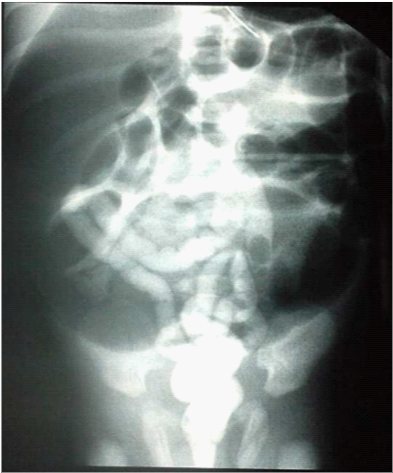

A girl weighing 3,050 Kg was delivered with a gestational age of 41 week. At the 2nd day of life she was admitted for neonatal occlusion with abdominal distension, bilious vomiting, and failure to pass meconium. Physical examination revealed a distended abdomen, no associated anomalies was founded. Abdominal X-Ray showed distended bowel, air fluid levels, with no air in the rectum (Figure 1). Surgical exploration was indicated and revealed a total colonic atresia (Type III) located at 3 cm below the Bauhin’s valve (Figure 2). Colostomy was made with proximal colic biopsy that indicate normal colic segment with presence of neuroganglionnary cells, colic continuity was restored 6months later with resection of a segment of the proximal dilated colon, with uneventful follow up.

Figure 1 Abdominal films with distended bowel.